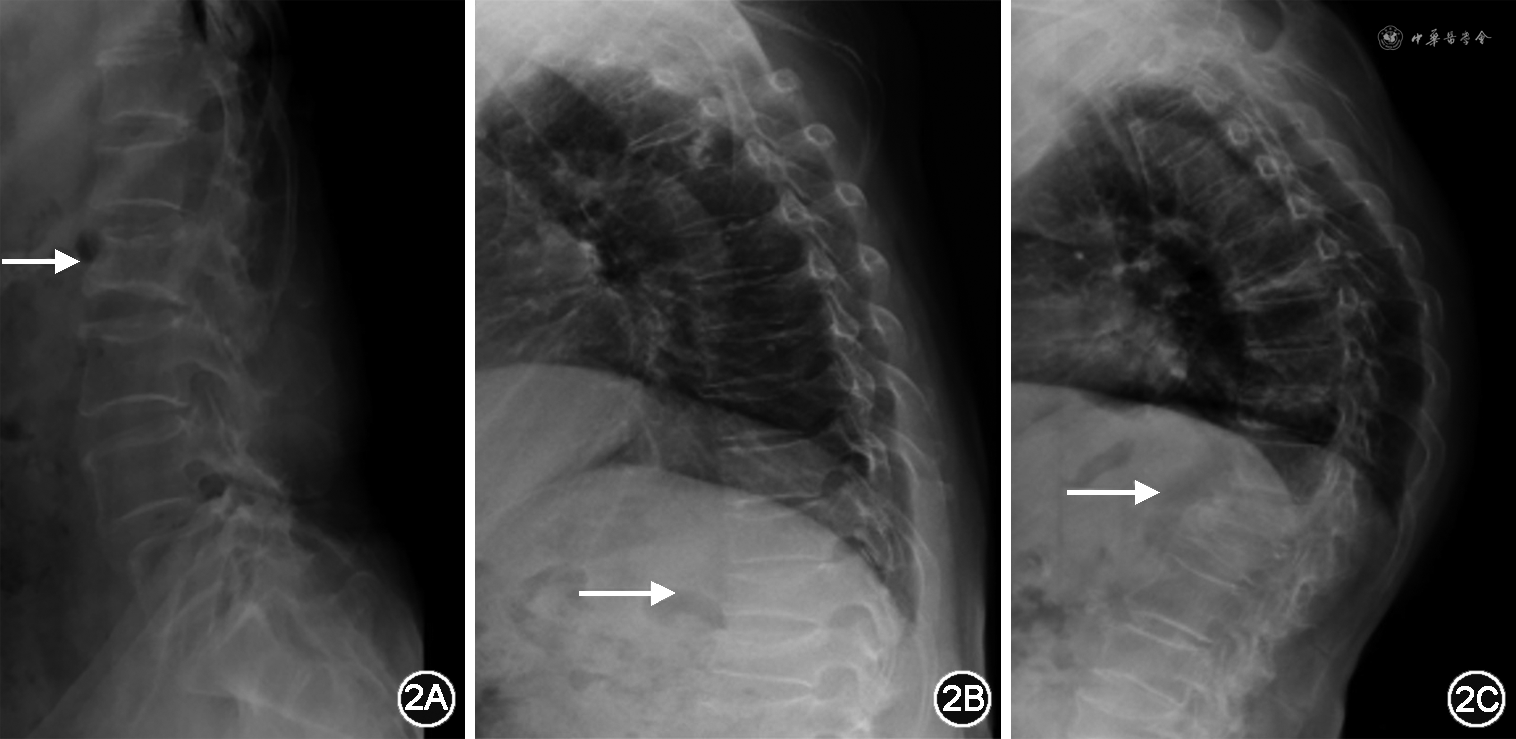

1.X线片:X线片是骨骼疾病诊断与评估最常用的影像学方法。骨质疏松时X线片主要表现为骨皮质菲薄,骨小梁稀疏、变细,骨质透明度增加,以椎体和骨盆表现明显,特别是负重胸椎和腰椎,椎体呈楔形改变或双面凹陷,骨小梁呈垂直栅状排列,也可见椎体压缩性骨折。普通胸、腰椎正侧位X线片是骨质疏松症椎体压缩性骨折及其程度判定的首选方法。基于胸腰椎侧位X线影像并采用Genant目视半定量判定方法[13],椎体压缩性骨折可分为3型、3度(图1)。3型分别为楔形骨折、双凹骨折和垂直压缩性骨折。3度分别为Ⅰ度即轻度骨折,原椎体高度压缩>20%~<25%;Ⅱ度即中度骨折,原椎体高度压缩了25%~40%;Ⅲ度即重度骨折,原椎体高度压缩>40%。X线片诊断骨质疏松症具有经济、方便、快捷的优点,可全面观察骨的形态、结构,是脆性骨折尤其是椎体骨折的首选检查方法(图2)。X线片检查设备成本较低,且能够进行全身各部位成像,因此在基层医疗机构普及率高。但敏感度和准确度均较低是其缺陷所在,只有当骨矿物质减少达30%~50%以上时,X线片才能有阳性表现[14]。此外,X线片不能量化评估骨密度,只能作定性判断,故X线片不用于骨质疏松症的早期诊断[15, 16, 17],且其判读受主客观因素影响大,故不能用于骨质疏松症的筛查和评估。